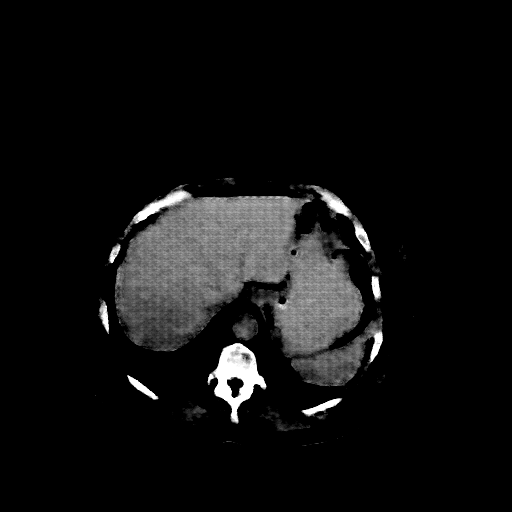

Original VENOUS CT scan

Full window (WL 1023.5, WW 4095 β Low β1024, High +3071)

Actual HU range: [-160.0, 240.0]